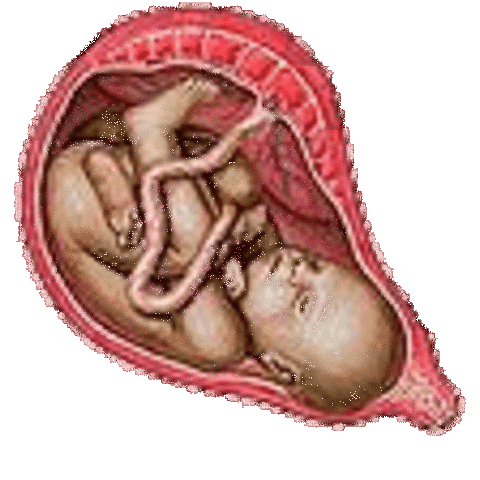

baby may drop in to the birth canal

• The baby's body is becoming chubby as fat layers build.

• Between now and birth they may gain about an ounce a day

• You may feel contractions of the womb

• The baby may have reached its final birth position.

• Most babies are born head first with only about 3 percent coming out feet first.

• About one in eight births are caesarean.

• The average baby is about 20 inches (51 cm) and weighs about 7.5 pounds (3400 grams).

• The baby has reached its final birth position.

• It will be cramped inside your uterus for much movement.

• Your baby will continue to punch and kick but lower in your abdomen, under your pelvis.

• The head is about 4 inches (10 cm) in diameter.

• Most of the baby's downy coating of lanugo has now disappeared.